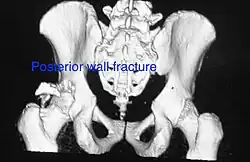

To understand the fracture pattern of a fractured acetabulum, it is essential to have minimum three x-ray views, though use of CT scan with 3-D reconstruction of images has made understanding of these fractures easier.

Posterior wall This is the most common variety of acetabular fracture. It typically occurs due to dashboard injury; when a person travelling in a vehicle involved in a head-on collision, the force applied over the flexed knee travels along the femur bone to the head of the femur, breaking the posterior wall of the acetabulum. The head of the femur is dislocated outside the joint. T shape When a transverse fracture also had a vertical fracture line, it is called a T shape fracture. Here the innominate bone is broken in such a way that all three parts of it, the ilium, the ischium and the pubis are separated from one another. This is a three part fracture. Though both columns are broken, the weight bearing dome is still attached to the main part of the ilium and hence it is not a true fracture of both columns.

Fractures of the acetabulum occur when the head of the femur is driven into the pelvis. This injury is caused by a blow to either the side or front of the knee and often occurs as a dashboard injury accompanied by a fracture of the femur.[1]